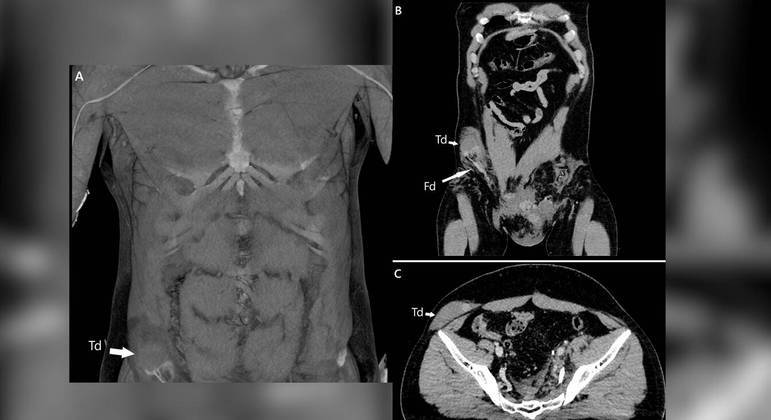

Tomografia mostra testículo alojado no abdômen do paciente – Foto: Reprodução/NDTomografia mostra testículo alojado no abdômen do paciente – Foto: Reprodução/ND

O impacto do acidente foi tão grande que a pressão gerada moveu o testículo do paciente por um canal na virilha que mede de 4 a 6 centímetros, causando fortes dores no homem, o que levou ao diagnóstico.

Essa passagem, conhecida como canal inguinal, forma-se à medida que os órgãos genitais externos saem do abdômen, onde se desenvolvem inicialmente no embrião.